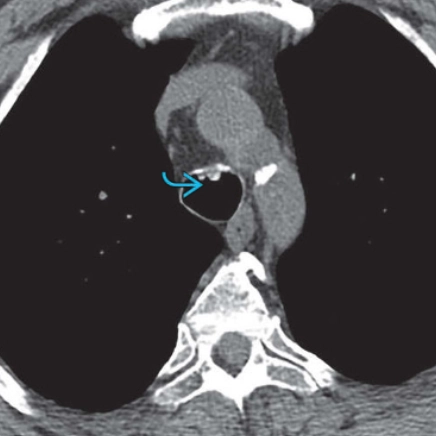

Khí quản hình vỏ kiếm (Sabre-sheath trachea)